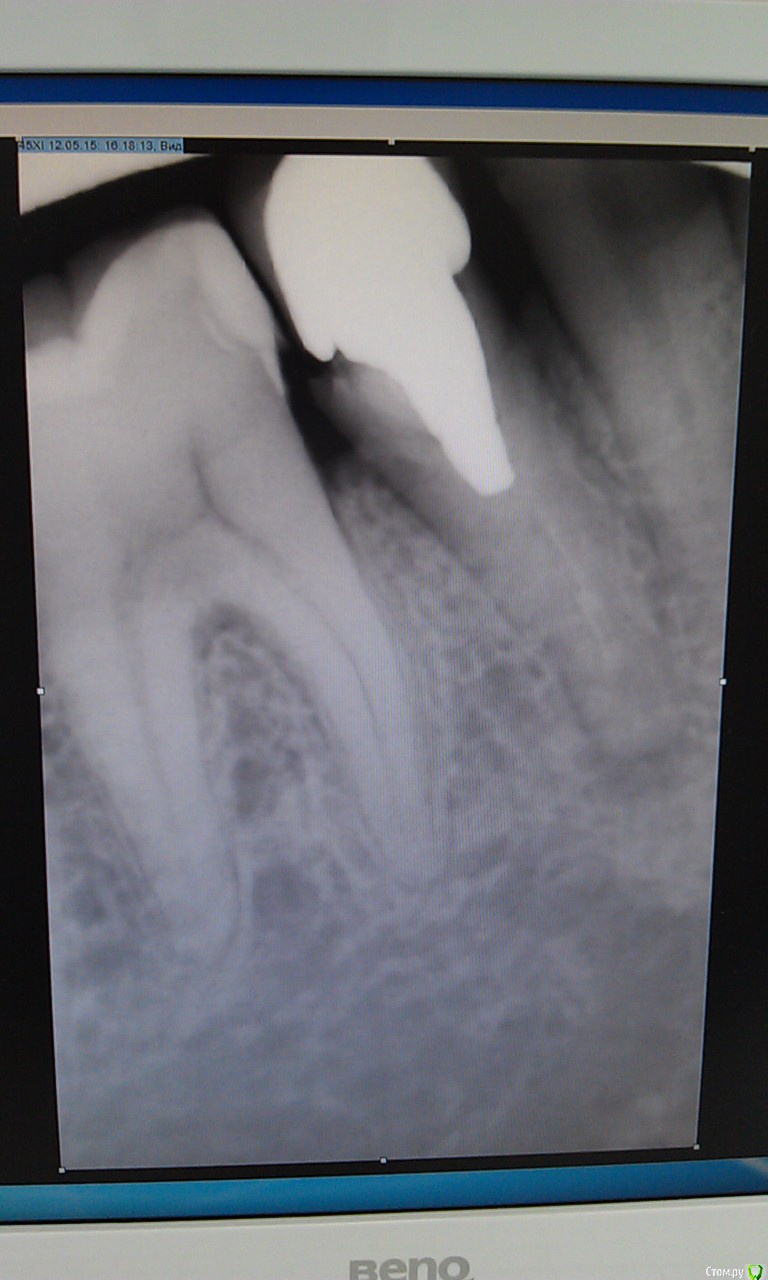

Валерия482 Опубликовано 12 мая, 2015 Поделиться Опубликовано 12 мая, 2015 Я человек очень далекий от стоматологии, по этому могу допускать ошибки в терминологии=)Ситуация:есть корень с культиевой вкладкой и коронкой на ней(металлокерамика), живу с этой конструкцией около 12 лет. 08.05.15 десна у корня отекла, появилась чувствительность зуба при прикусывании.10.05.15 появилась небольшая подвижность зуба, отек десны уменьшился.1 стоматолог (08.05) изучив снимок (на руках отсутствует) порекомендовал: удалить коронку, высверлить вкладку (успех 50 х 50), пролечить периодантит и далее в обратном порядке.2 стоматолог (12.05) изучив снимок (фото снимка прилагаются) вынес вердикт "удалять".Я на распутье, т.к. не могу решить что же делать.Помогите пожалуйста советом.Спасибо! Ссылка на комментарий

Гарриевич Опубликовано 13 мая, 2015 Поделиться Опубликовано 13 мая, 2015 + за перелечиваниевкладка короткая, извлечь ее будет достаточно просто Ссылка на комментарий